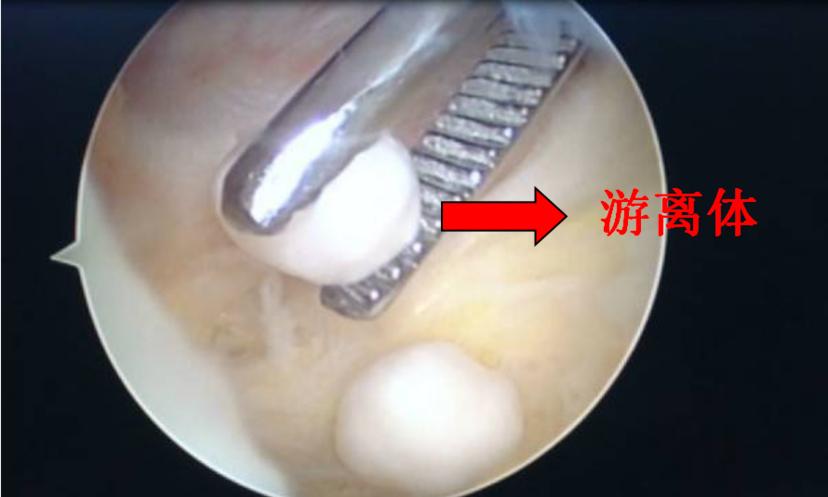

①膝关节镜清理术:通过关节镜手术清理膝关节内游离体(软骨碎片)、修复损伤退变半月板等,能减轻部分骨关节炎患者症状,适用于伴有关节内游离体或者半月板损伤退变的早、中期骨关节炎患者。